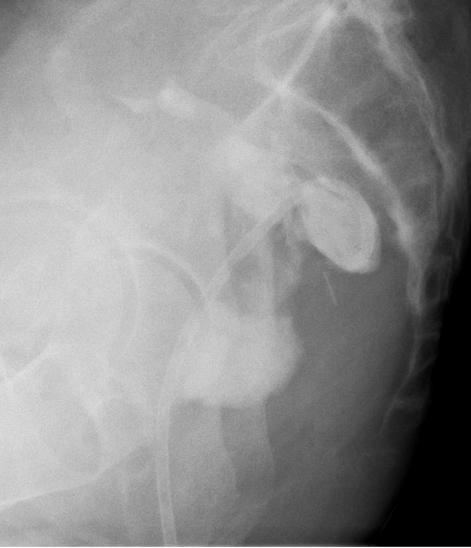

同直肠相临的脓肿可能可以经直肠引流。经直肠入路进行外科手术引流的方法已经比较成熟,但一般需要全身麻醉并且要求经直肠能够触到脓肿。在影像引导下进行引流就能克服这些问题,并且有多种手段可以进行这种引导。透视引导的引流就是在肛镜或一个改良的enema tip下插入针头。也可以采用CT引导。

最早描述的超声引导方法是经腹的,最近已经出现了经直肠超声并且可以同透视联合应用。 US-Guided Transrectal Drainage:Seldinger technique

在直肠前部或后部的脓肿都可以经直肠引流。不要求可以触到脓肿。使病人处于左侧卧位,在影像监控下将针头插入直肠,针头原来是回缩在它的鞘里的。可以用带着手套的手指,塑料管,或活检导轨贴附在经直肠探针上,根据采用的影像学方法帮助针头的定向。整个过程几乎是无痛的,并且可以有相当好的耐受。通常不必要进行局麻和静脉用镇静剂。在使用锁定导管(locking catheter)时,不需要固定皮肤,但病人下地活动时就必须固定皮肤了。

没有B超引导也可以考虑在透视引导下直接穿刺